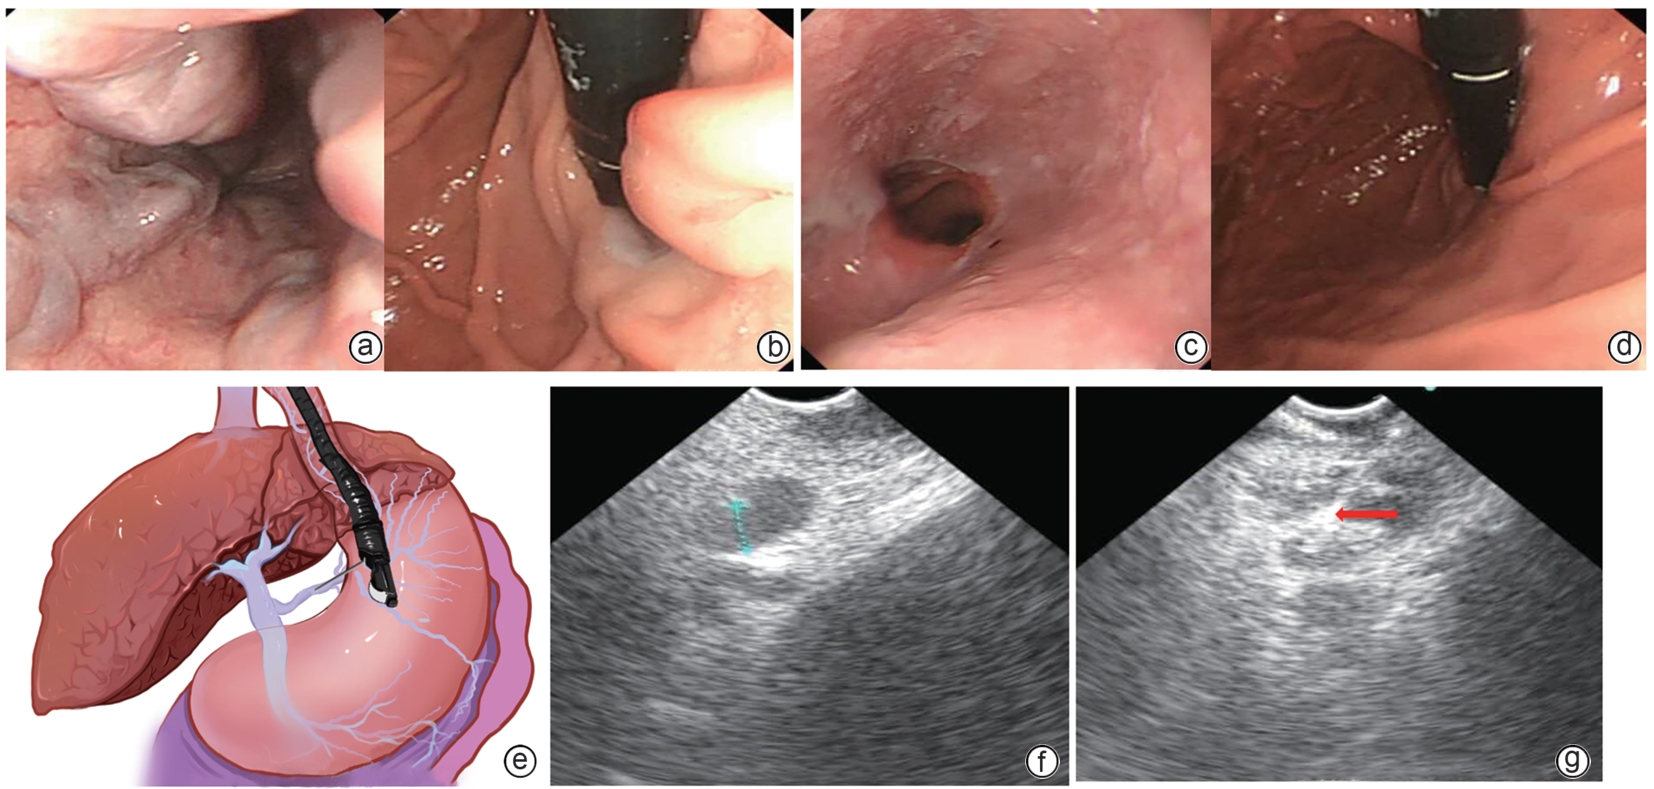

•   Objective  To investigate the safety and efficacy of puncture cyanoacrylate selective seal (PCSS) under endoscopic ultrasound in the treatment of gastroesophageal varices (GOV).  Methods  A total of 100 patients with liver cirrhosis who underwent endoscopic therapy for the secondary prevention of GOV bleeding in Beijing Ditan Hospital, Capital Medical University, from March 1 to December 31, 2023 were enrolled and randomly divided into PCSS group and traditional endoscopy group. The patients were followed up for 6 months after surgery, and the two groups were compared in terms of clinical outcome and complications. The primary outcome measure was the rate of alleviation or disappearance of GOV, and the secondary outcome measure was variceal rebleeding and death. The independent-samples t test was used for comparison of normally distributed or approximately normally distributed quantitative data between two groups, and the Wilcoxon non-parametric test was used for comparison of non-normally distributed quantitative data between two groups; the chi-square test or the Fisher’s exact test was used for comparison of qualitative data between two groups.  Results  There were 50 patients in the PCSS group, among whom 1 patient was lost to follow-up, and there were 50 patients in the traditional endoscopy group, among whom 3 patients were lost to follow-up. There were no significant differences between the two groups in baseline data such as age, sex, Child-Pugh class, varices grade, and GOV typing (all P>0.05). Compared with the traditional endoscopy group, the PCSS group had significantly better results of the number of endoscopic treatment sessions (t=-15.671, P=0.001), the total amount of tissue adhesive used (t=-2.830, P=0.006), and the rate of alleviation or eradication of varices sclerosis (χ2=7.078, P=0.029). Both groups had low rates of postoperative rebleeding, adverse reactions, and complications, and there were no significant differences between the two groups (all P>0.05).  Conclusion  Compared with traditional endoscopy, PCSS can significantly enhance treatment outcome while maintaining safety standards.